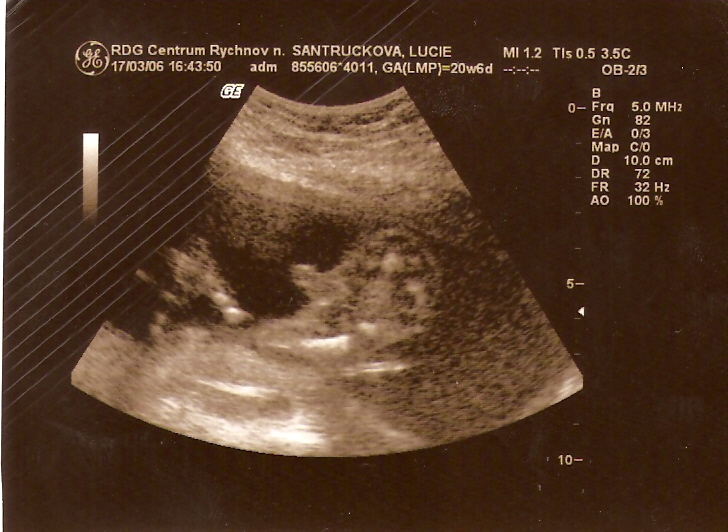

...podruhé 17. BŘEZNA 2006 /21. týden/(den před svatbou maminky s tatínkem) jsem měřil už 20 cm a vážil 418 g....Už bylo zřejmé, že budu KLUK jako BUK....